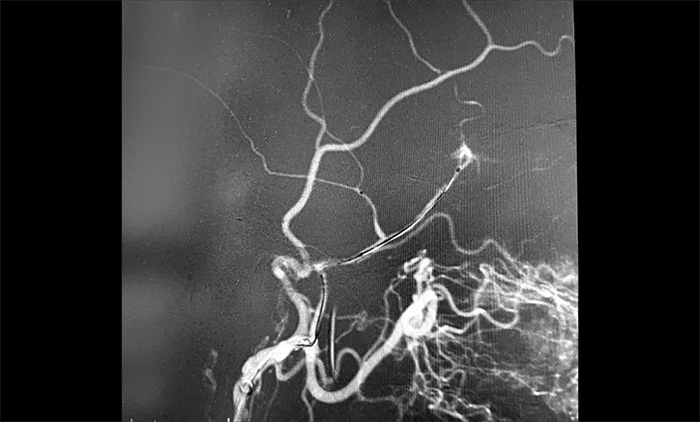

12月29日,顺利进行手术。术中,王贵平博士在介入团队协助下克服血管迂曲的困难,导管精准到达左脑膜中动脉前支、左脑膜中动脉后支,之后缓慢注入液体栓塞剂,栓塞剂逐渐向脑膜中动脉主干反流,复查造影,左脑膜中动脉无明显前向血流,手术成功。术后,患者无新发神经功能缺损。言语不清,肢体活动不利,头晕等症状逐步好转。

▲ 术中

▲ 顺利栓塞脑膜中动脉